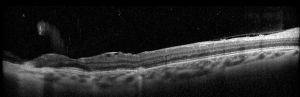

- OCT shows loss of continuity of RPE at the site of rupture with thinning of underlying inner choroid.